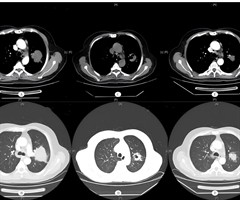

肺鳞状细胞癌合并多系统免疫相关不良反应1例

患者,男,69岁,因“刺激性干咳、咳血2月"于2021年2月25日初诊于我院。行胸部增强CT检查提示左肺上叶有一团块影,约为5.5cm×5.0cm×4.3cm 大小,不均匀强化,与左肺动脉干关系紧密,左肺上叶舌...